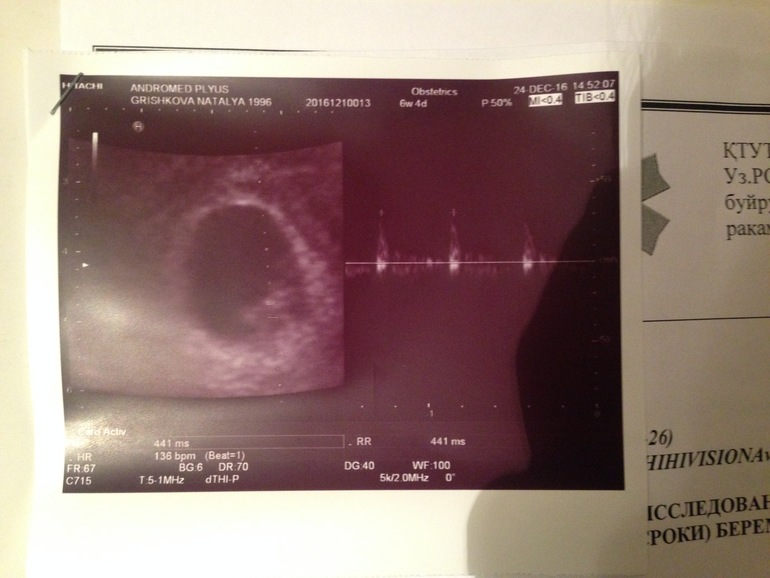

Беременность- 1 триместр ( только до 10 недель)Вот я и дождалась своего УЗИ!) Очень волновалась и переживала а вдруг что ни будь не так, вдруг сердечко не будет стучать. Легла на кушетку, УЗИст стал смотреть и очень нас стал хвалить!) мы молодцы! Мы растем, нам 6 неделек, мы уже 1см и сердечко наше 136 ударов) как увидела эту точечку на экране пульсирующую, чуть не заплакала) Вышла с кабинета с легкой душой! Токсикоза не наблюдаю) иногда подташнивает, все терпимо) Стала часто бегать писать. Не переношу творог. Постоянно хочу жаренную курочку!) Частая усталость и вялость, с работы сразу прихожу засыпаю. Недельку назад были тянущие ощущения внизу живота. Назначили свечи папаверин и витамины магний В 6 премиум. Все прошло слава богу!) запоры мои закончились ттттт! Единственное что...не могу спать с мужем. Постоянные неприятные ощущения и жжение. Завтра иду к гинекологу, брать лист на анализы и по поводу интим вопроса. Вот такой отчет на 6ой недельке! И наше фото пузожителя!)